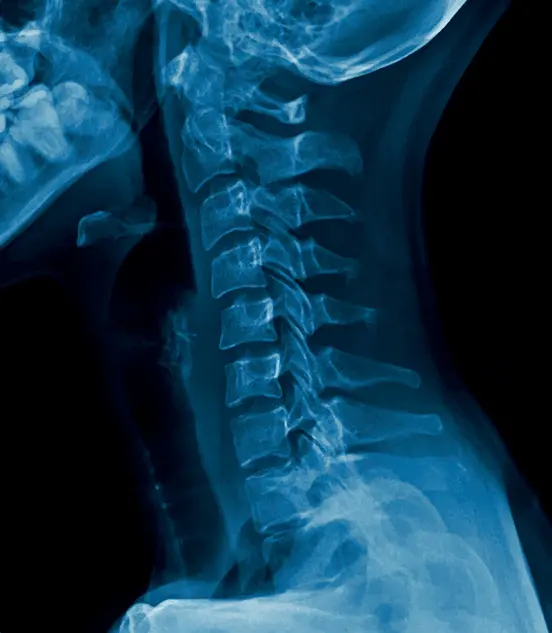

Our remote reporting Service ensures seamless operations for our client-partners by extending coverage beyond regular hours. We provide extended hours Service coverage, ensuring reports are delivered at best-in-market turn-around times for routine cases, with expedited options for urgent needs. This ensures swift patient care decisions, ultimately improving patient outcomes.